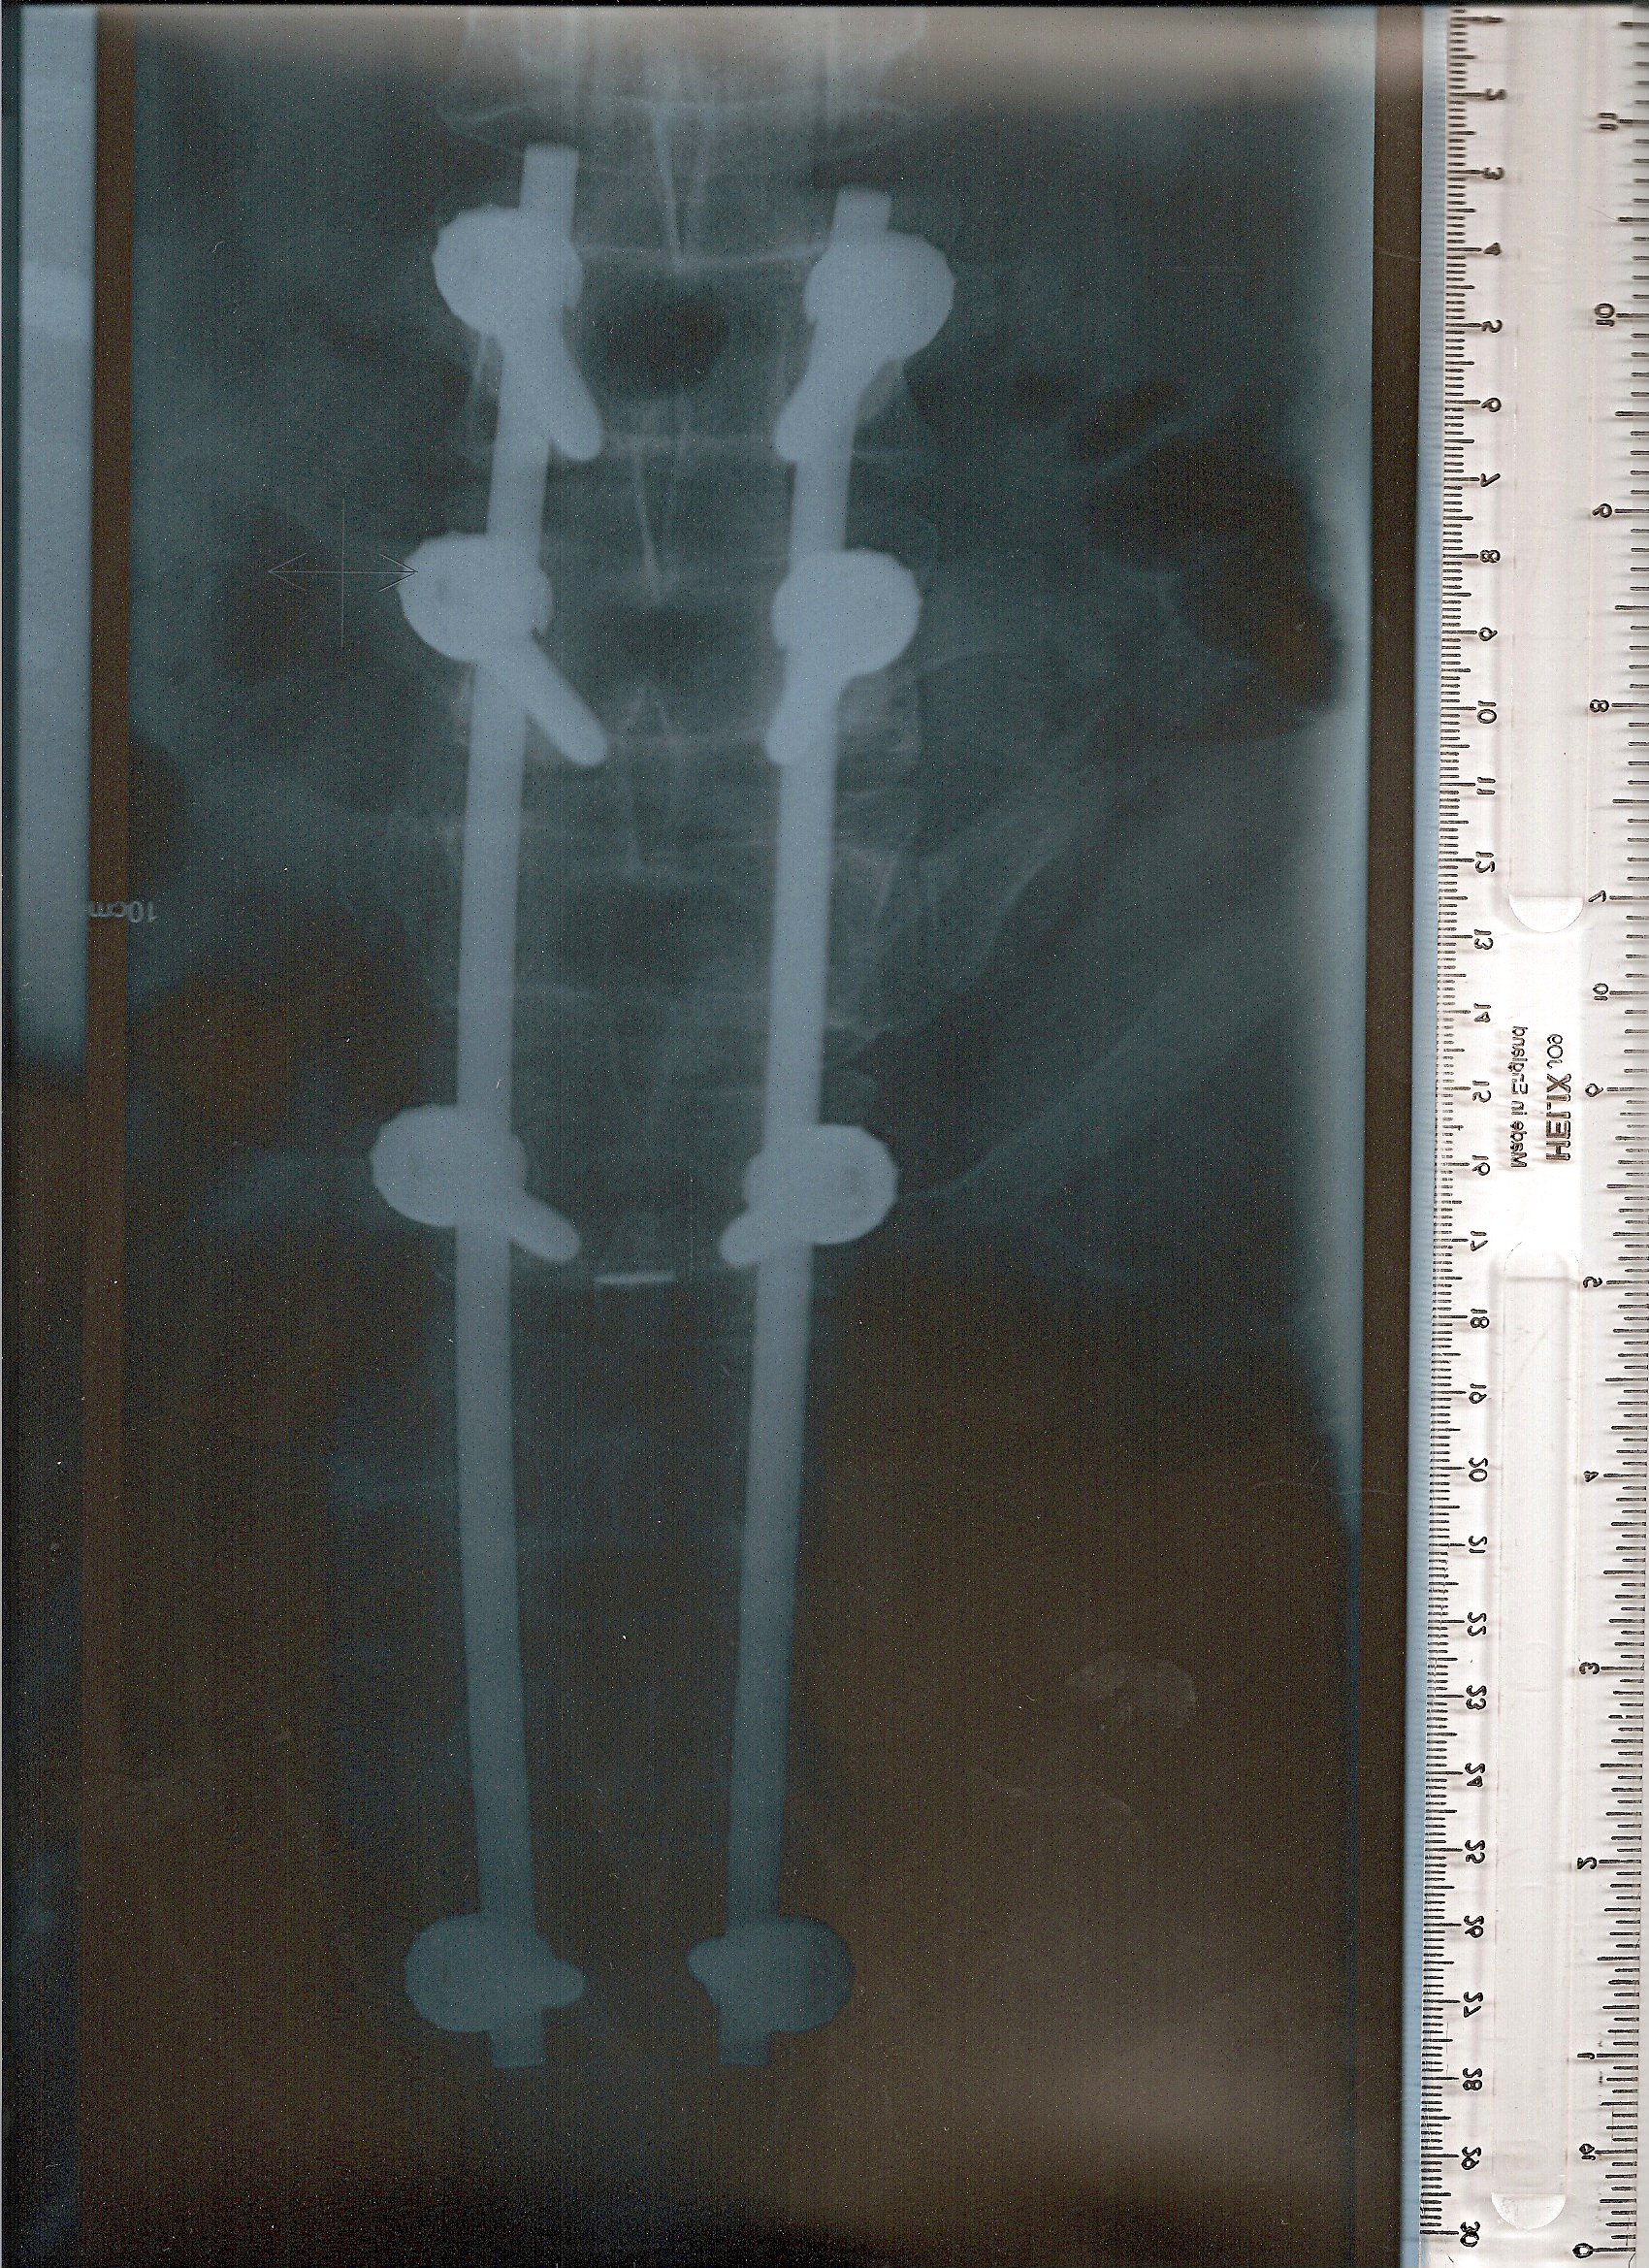

Before And After Surgery For Blount's Disease